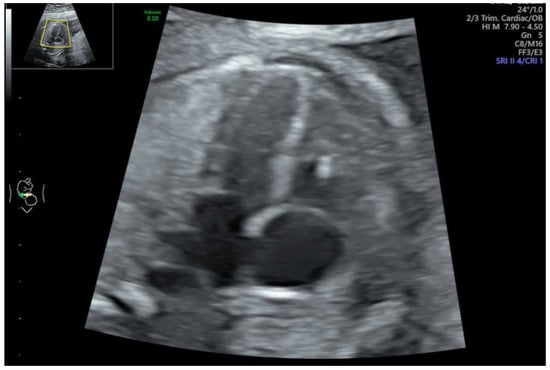

2.1. Defining of Functional Abnormalities